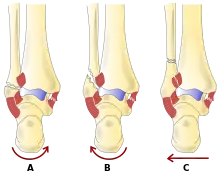

- La classification de Lauge-Hansen (en) classe les fractures selon le mécanisme de la blessure en fonction de la position du pied et de la force de déformation (le type le plus courant est la supination-rotation externe).

- La classification Danis-Weber (en) classe les fractures de la cheville selon le niveau de la fracture de la fibula distale (type A = en dessous du ligament syndesmotique, type B = à son niveau, type C = au-dessus du ligament), avec une utilisation dans l'évaluation des lésions de la syndesmose et la membrane interosseuse.